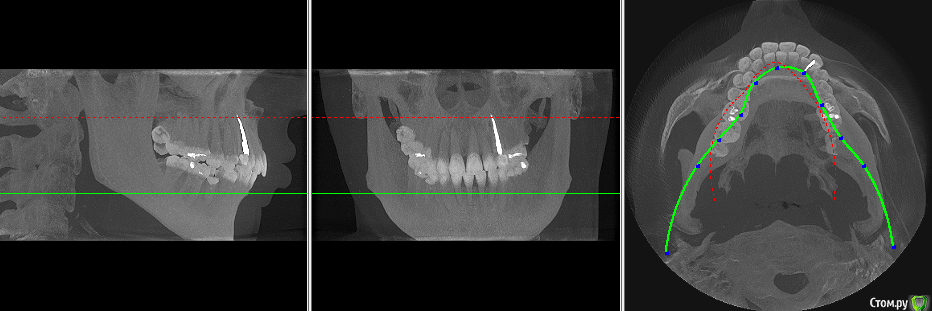

veraprok Опубликовано 25 июня, 2015 Поделиться Опубликовано 25 июня, 2015 У сына зубы разрушаются безболезненно. При этом на зубах какие-то белые "шапочки", которые видны на снимках, которые я прикрепила к сообщению.Зуб разрушается так, как будто кто-то снимает с него всю эмаль, оставляя только то, что в середине.Один только раз у него была боль, но болел висок, и он обращался к невропатологу, и его лечили от невралгии лицевого нерва, а это был зуб верхней челюси, когда его пролечили, боль прошла.Но во всех остальных случаях он не замечает разрушения зубов, так как зуб может быть разрушен до основания, но не болит.У него проблемы со щитовидной железой. Не знаю, влияет ли это, но на всякий случай сообщаю.Что это и как с этим бороться? Потому что разрушение всех зубов идет быстрыми темпами., и я боюсь, что он потеряет все зубы. Ссылка на комментарий

faity Опубликовано 25 июня, 2015 Поделиться Опубликовано 25 июня, 2015 белые шапочки на снимках это и есть эмаль, при болезнях щитовидной железы бывают проблемы с зубами,но это индивидуально. не надо ждать пока заболят зубы, посещайте стоматолога раз в полгода или чаще, делайте диагностические снимки и обследования, и брекеты поставьте. тогда и сустав перестанет болеть и зубы крошиться, гипернагрузка это плохо Ссылка на комментарий

veraprok Опубликовано 25 июня, 2015 Автор Поделиться Опубликовано 25 июня, 2015 Да нет же, я такого никогда не видела - чтобы эмаль была нестественно белого цвета! Причем, если зуб "помечен" такой шапочкой, но еще не начал разрушаться - это уже как метка, что очень скоро разрушится.Извините, я ждала конструктивного ответа, а не общих слов. Ссылка на комментарий

veraprok Опубликовано 25 июня, 2015 Автор Поделиться Опубликовано 25 июня, 2015 Целых три фото прикреплено!!! Вы разве их не видите?! Ссылка на комментарий

faity Опубликовано 25 июня, 2015 Поделиться Опубликовано 25 июня, 2015 Целых три фото прикреплено!!! Вы разве их не видите?! я вижу 3 рентгеновских снимка и ни одной фотографии!!! вы разве не прочитали то, что вам написал я и мой коллега?! Ссылка на комментарий

Scrabble Опубликовано 25 июня, 2015 Поделиться Опубликовано 25 июня, 2015 Белые шапочки на рентгене-это эмаль. Сфотографируйте зубы в полости рта. Сколько лет сыну? Ссылка на комментарий